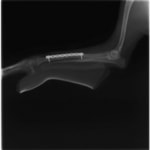

トイプードル 右遠位橈尺骨短斜骨折のALPSによる内固定

Locking Compression Plate

LCPは、スクリュー(ネジ)とプレート(金属の板)をロックする特殊な構造により骨折部位を固定する新しい世代のプレートシステムです。ひとつのホールでロッキングスクリューとスタンダードスクリューの使用を選択できるユニークな構造をしているため、骨折断端間の圧迫を目的とした従来型プレート固定法に加え、高い角度安定性を有するロッキングスクリューを用いた固定法の選択が可能です。従来のプレートシステムでは困難だった部分の骨折や癒合不全の症例に高い治療効果をもたらします。